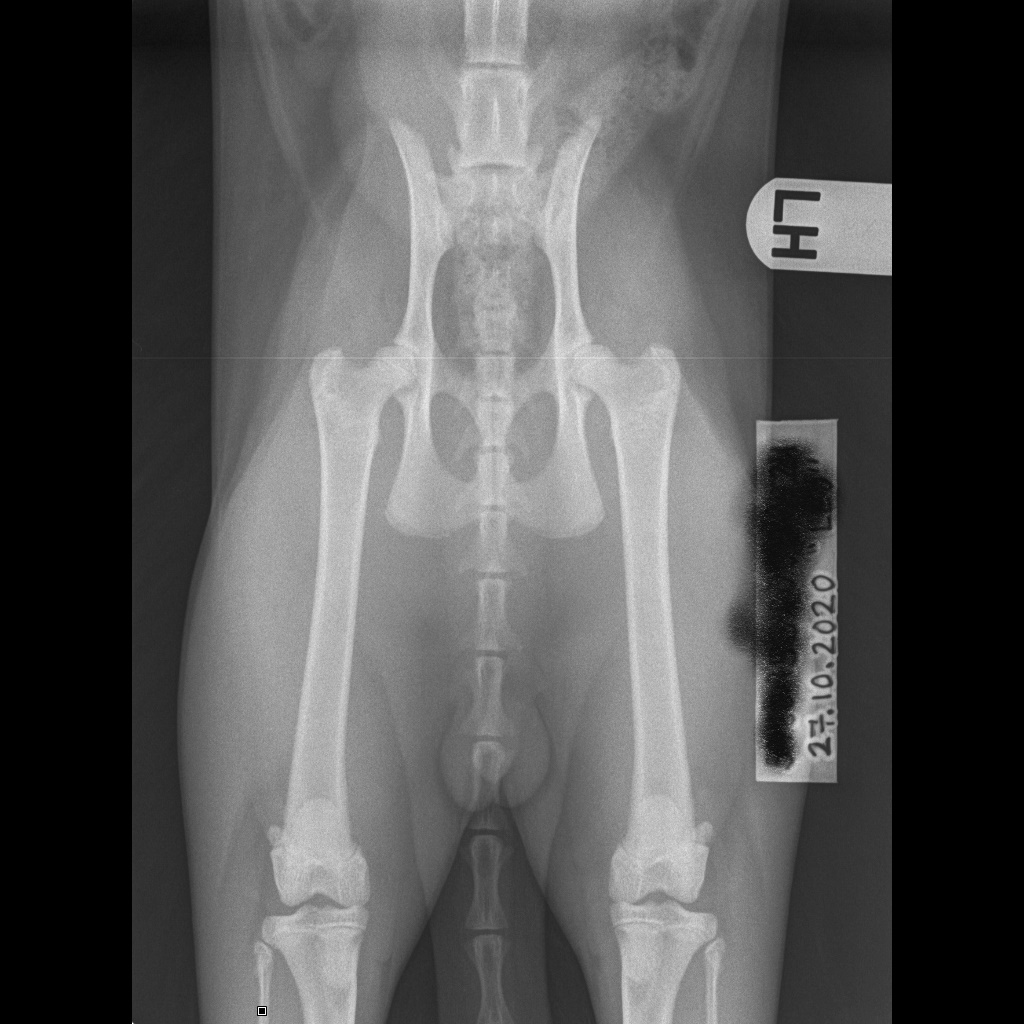

I den siste tiden har fire av kattungene fra kullene i sommer gjennomført HD – røntgen. Resultatet var veldig bra for tre, men Aelia kunne hatt bedre hofter. Alle bildene ble sendt til OFA for vurdering.

NO*Blue Warrior Aelia – Mild NO*Blue Warrior Maximian – Good NO*Blue Warrior Cedi – Good NO*Blue Warrior Warrior A Million Dollar baby – Good

Hoftebildet øverst er James Joyce sine, han er pappa til Cedi og Milli som har hvert sitt bilde under.